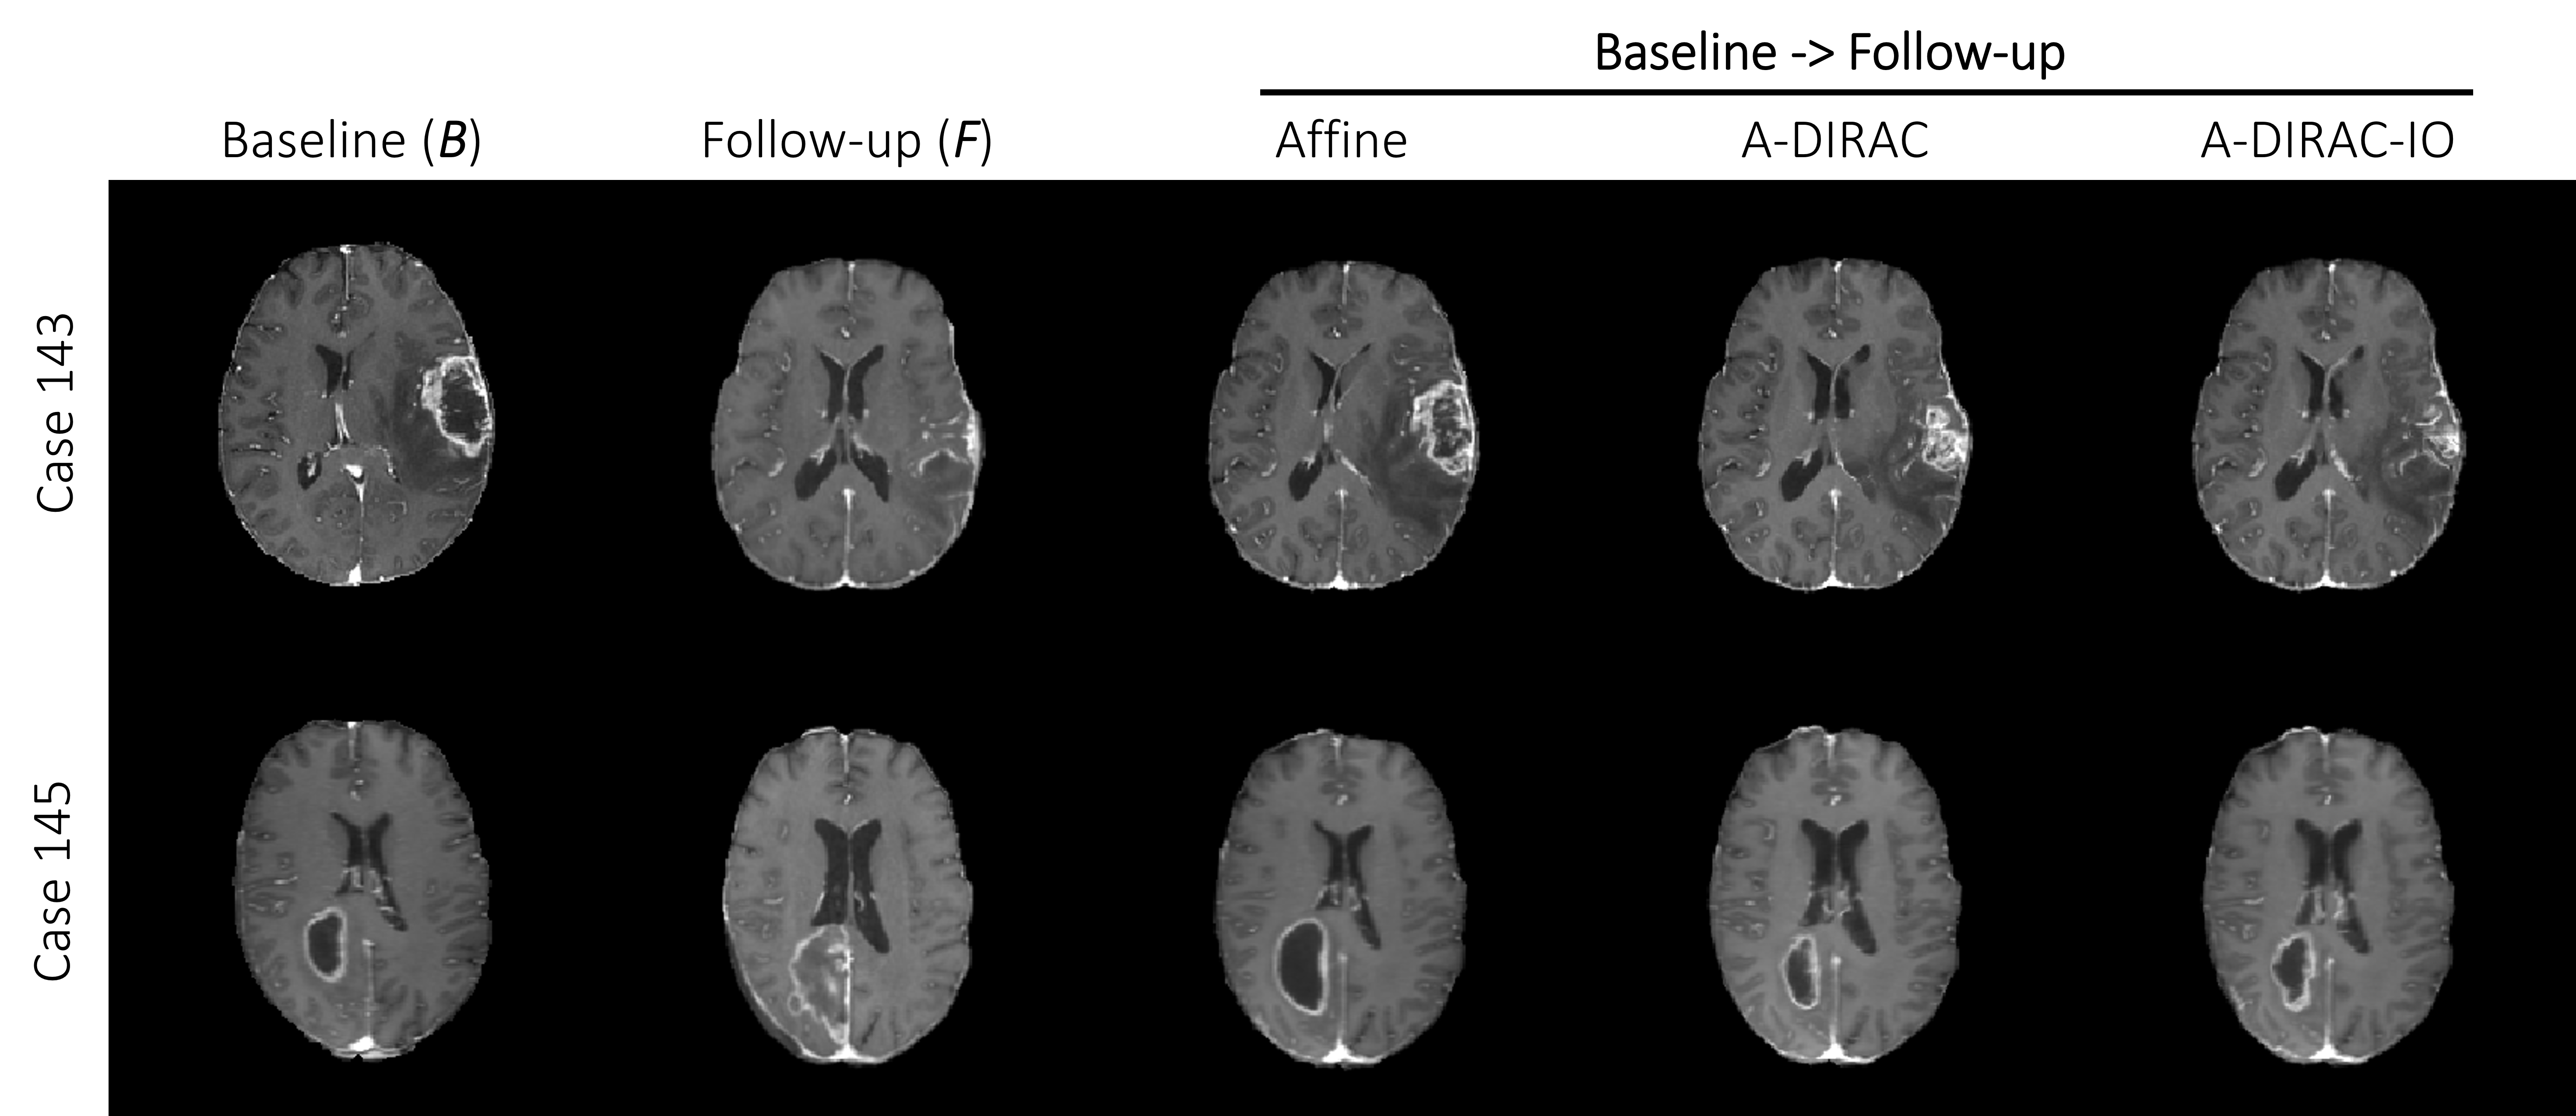

Refer to caption

Figure 4: Example axial T1ce MR slices of resulting warped images (B𝐡B to F𝐹F) from affine, A-DIRAC and A-DIRAC-IO registration methods.

An example qualitative result is shown in Figure 4. The reduction of the registration error in the validation set in the pipeline is shown in Table 3. While the MRI scans are pre-registered to a common template, the average median error is reduced from 7.8 mm to 4.18 mm, indicating there exists a large linear misalignment between each case. Furthermore, the median error and robustness are consistently improved after each step, reaching to 1.64 mm average median error. Notably, our MAE is the lowest on the challenge’s validation leaderboard.